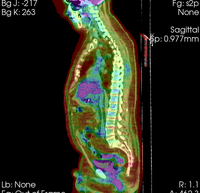

Slicer Registration Use Case Exampe #8: Intra-subject whole-body PET-CT

this is the fixed reference image. All images are aligned into this space lleft this is the moving image. The transform is calculated by matching this to the reference image LEGEND

lleft this indicates the moving image that determines the registration transform.

lleft whole body CT + PET baseline lleft whole body CT + PET follow-up

CT: 512 x 512 x 195

0.98 x 0.98 x 5.0 mm

PET: 168 x 168 x 195

4.1 x 4.1 x 5 mm